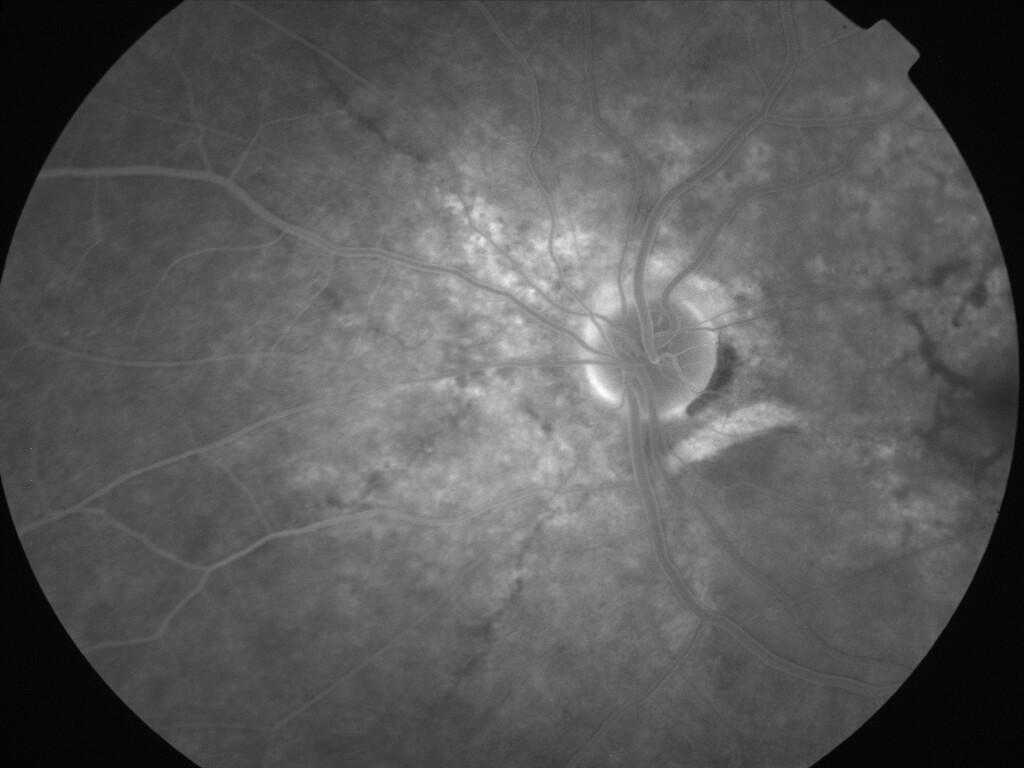

IMG0039.jpg